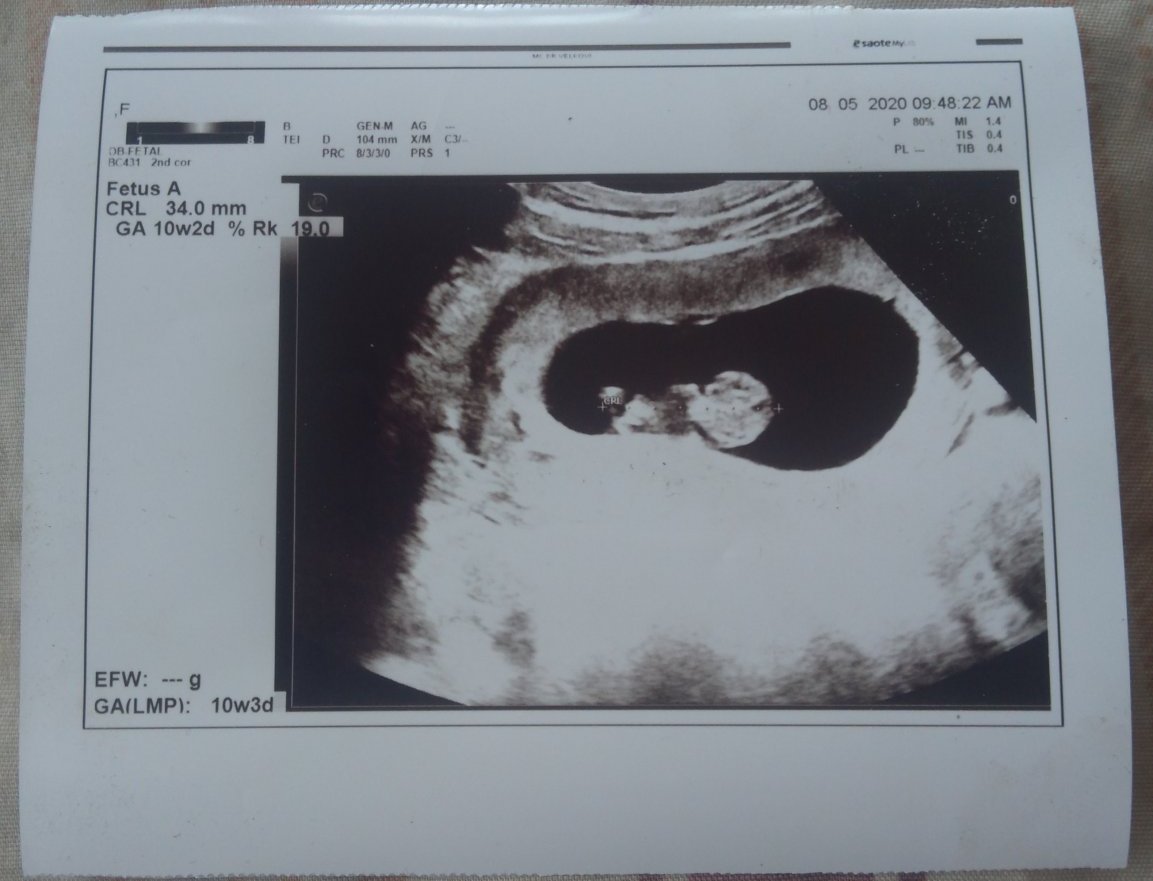

Отидох на преглед в Петък,защото в Четвъртък нямах възможност взех направлението и отидох при акушер-гинеколог той ме прие. Видях си детето на екрана пред мен и разбрах с точност на колко време съм на 10 седмици и 3 дена беше вчера,а днес 4. Той ми каза,че мога да направя аборт,но разбира се с присъствието на родител. Аз не бях казала още на майка ми само леля знаеше и така вчера се престраших и казах тя не реагира зле нито ми е крещяла,нито нищо. И сега в Понеделник ще отида в болницата със снимката на бебето,която гинеколога ми я даде и ще се разберем за датата на аборта. Благодаря за съветите,които ми дадохте сега само предстой аборта и всичко ще си бъде както преди. Пращам Ви и самата снимка,която ми е дадена от гинеколога.